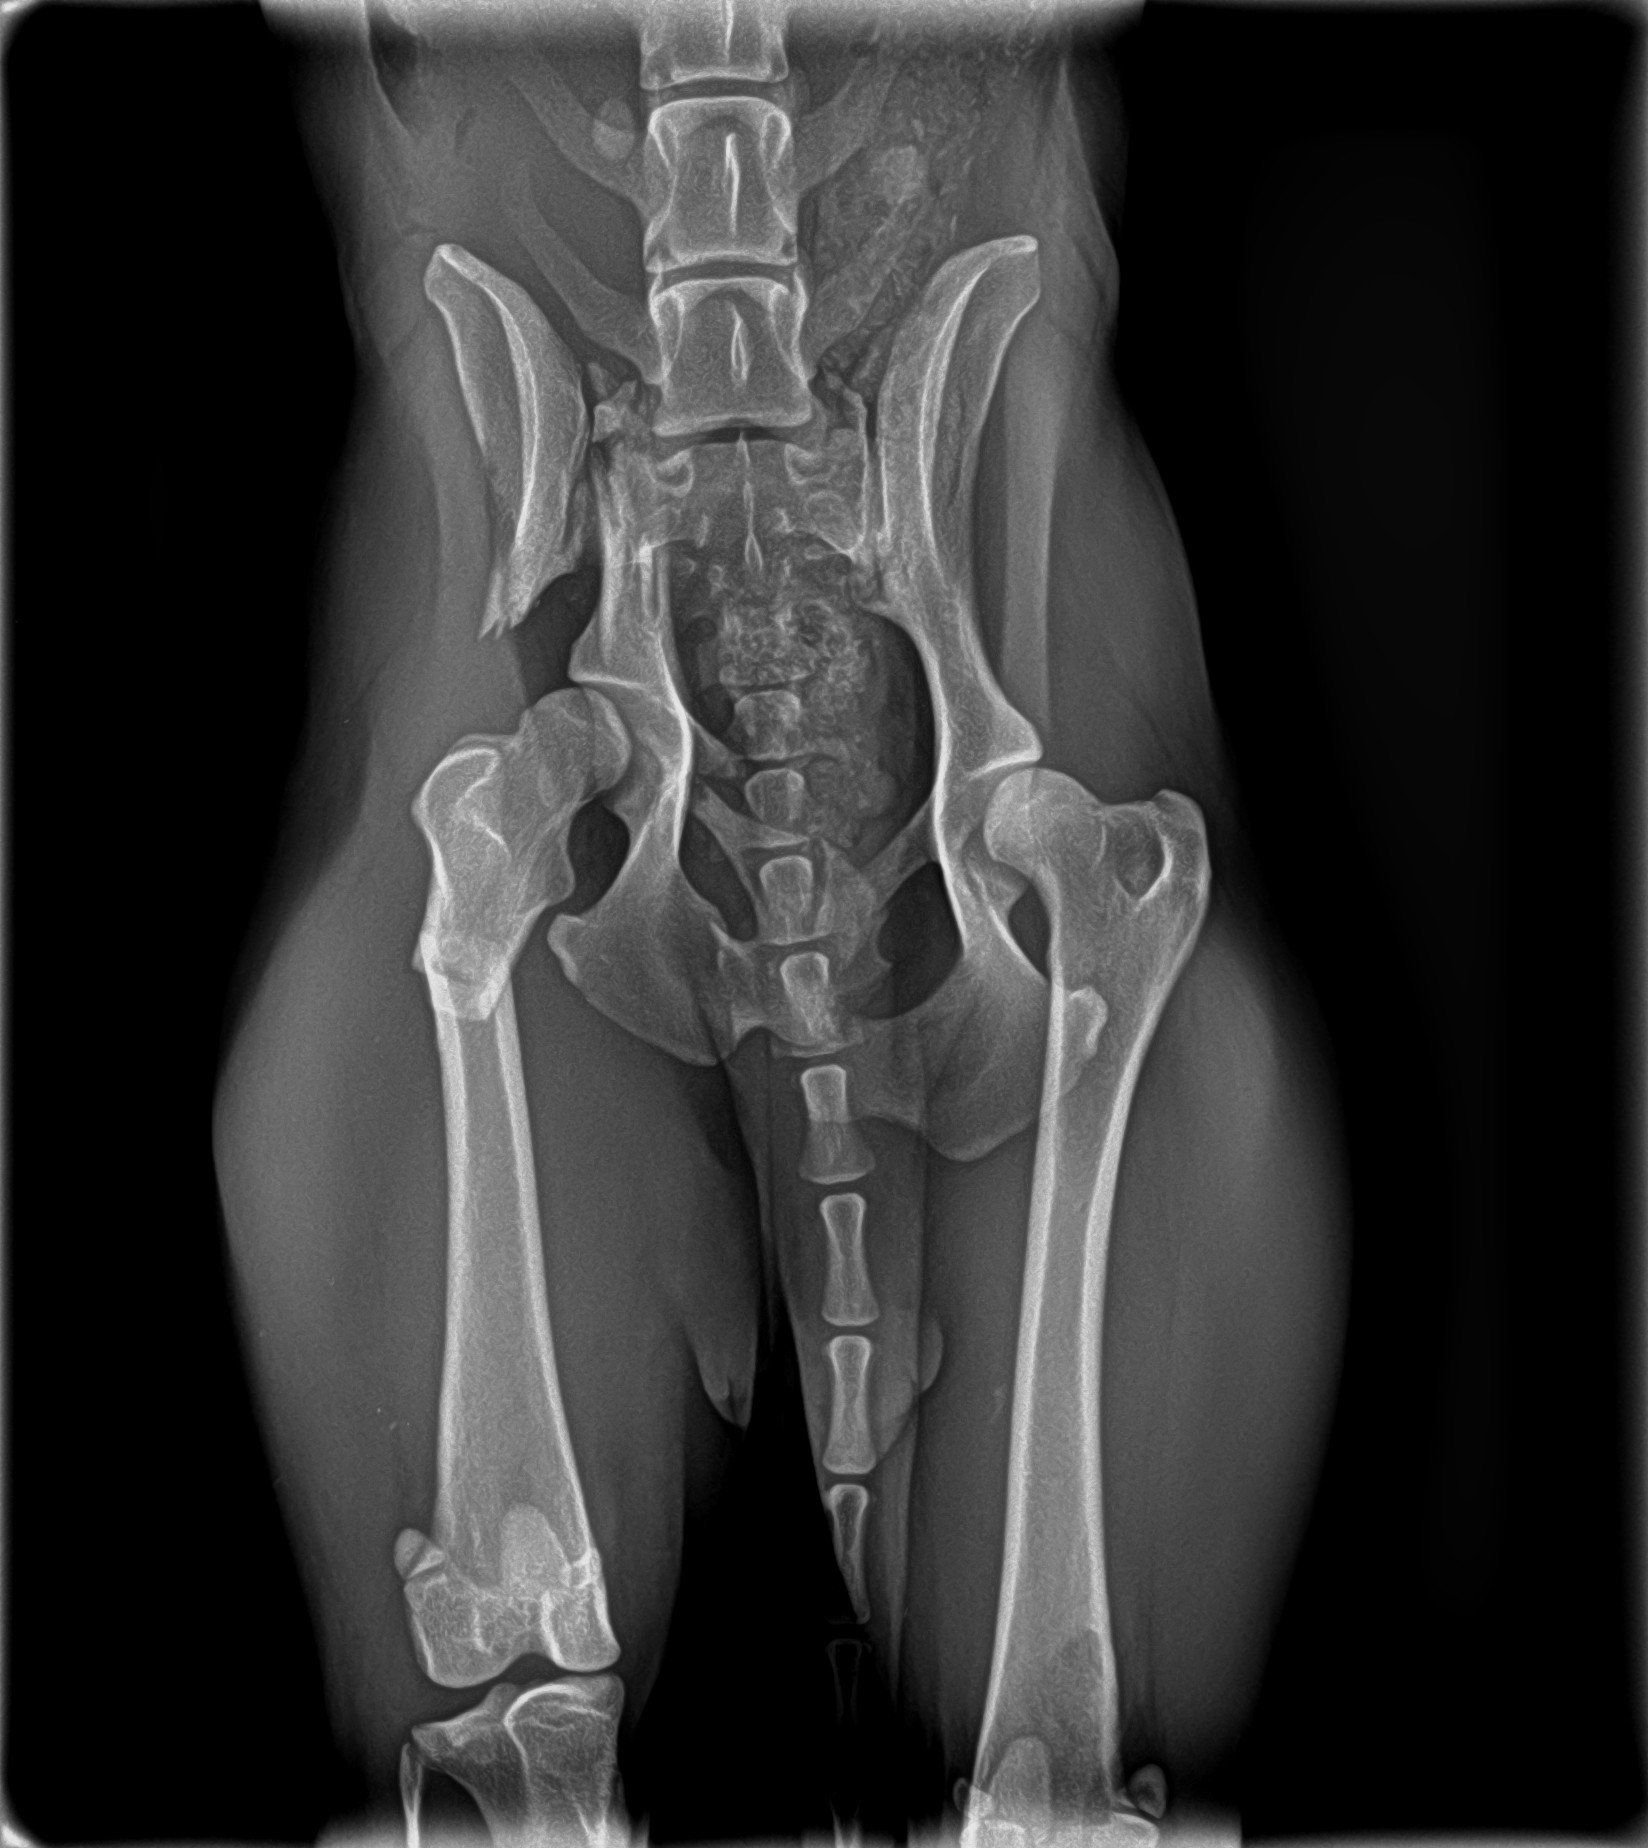

Sushy apareció atropellada en la carretera, de alli la llevaron a la perrera, donde querian sacrificarla, por suerte unas personas la sacaron y nos pidieron ayuda para ella, despues de traerla desde valencia ingreso en un hospital veterinario donde la operaron 3 veces, se paso varias semanas ingresada y cuando por fin salio a una casa de acogida se dio cuenta de que engordo en 3 dias y se le inflamaron las mamas.

Asi que la llevamos al veterinario y sorpresa sorpresa, nuestra peque estaba embarazada, como no podía tener un parto natural se programo una cesárea, pero se puso de parto 4 dias antes, asi que hubo que hacérsela de urgencias, por desgracias uno de los bebes no sobrevivió, pero Susho si que lo hizo y ella ha demostrado ser una super mami.

Busca acogida o adopcion, el 12 de mayo la vuelven a operar y esta se supone que ya es la ultima, nos han dicho que se va a recuperar por completo.